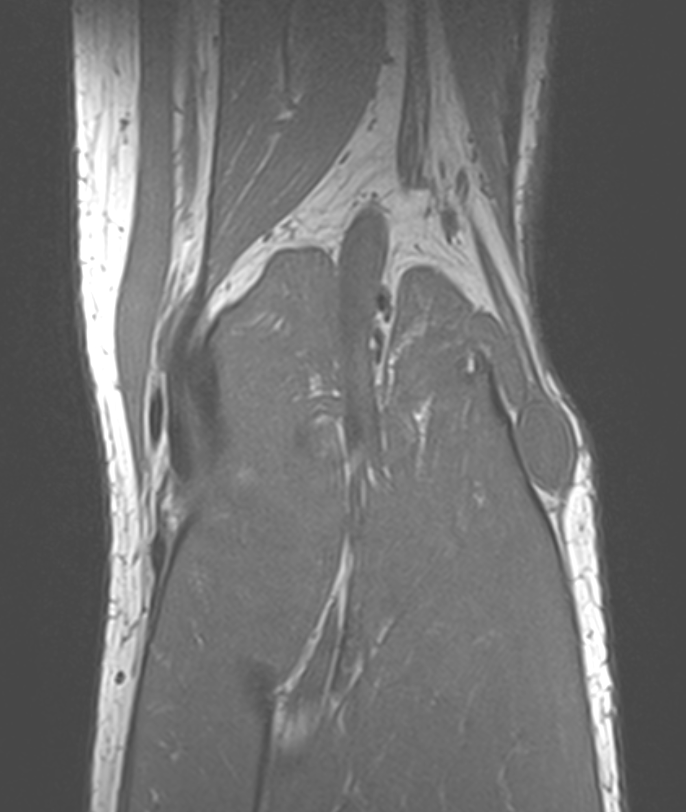

MRI

Target sign

- hypointense centrally

- hyperintense peripherally

Neurofibroma common peroneal nerve